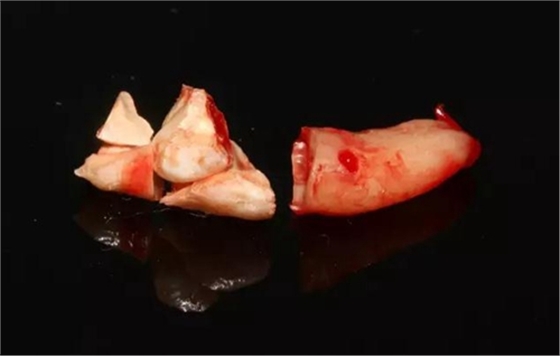

取出的離體43